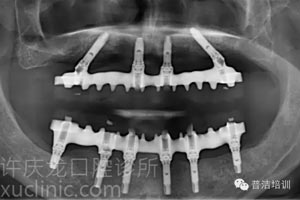

六、最終戴入患者口內(nèi)的牙橋X光

![]() |

可以看到:種植體與上部牙橋各部件精密貼合,種植體植入的位置、角度等都堪稱完美。牙橋與牙齦的接縫經(jīng)過特殊設(shè)計(jì)容易清潔,同時(shí)在說話或大笑的時(shí)候又不會(huì)露出來。